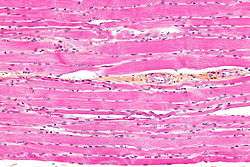

Striated muscle tissue is muscle tissue that features repeating functional units called sarcomeres, in contrast with smooth muscle tissue which does not. The presence of sarcomeres manifests as a series of bands visible along the muscle fibers, which is responsible for the striated appearance observed in microscopic images of this tissue. There are 3 types of specific striated muscles, these being:

Contractions in striated muscles are voluntary, except for the heart muscle, in which contractions are regulated involuntarily by the sinoatrial node. Cardiac muscle is often treated separately from the other striated muscles, as it has somewhat different characteristics.[1] During voluntary contractions, a striated muscle is extended by the action of an antagonistic muscle. All skeletal muscles are attached to some component of the skeleton, unlike smooth muscle which comprises hollow organs such as the intestines or blood vessels. The fibers of striated muscle have a cylindrical shape with blunt ends, whereas those in smooth muscle can be described as being spindle-like with tapered ends. Two other characteristics that differentiate striated muscle from smooth muscle are the facts that the former has higher amounts of mitochondria and contains cells that are multinucleated.[2]